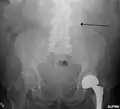

The faint outline of the calcified wall of an AAA as seen on plain X-ray

Abdominal aortic aneurysms (3.4 cm)